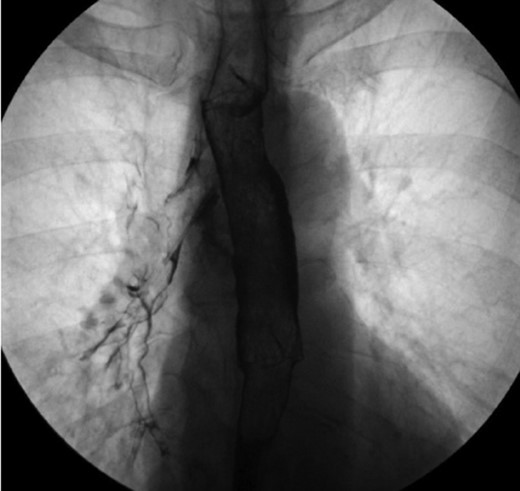

A rigid bronchoscopy was performed 8 weeks after the original endobronchial stent placement. The flexible bronchoscope was passed around the Y-stent to visualize the medial wall of the right mainstem bronchus. The site of the fistulous communication had improved ~80%, but a small residual defect was still present. Despite improvement in the size of the fistulous communication, the defect appeared be quite deep and did not show signs of apposition of the opposing walls of the fistula that would aid in healing. Additionally, there was concern that the Y-stent may have also have been contributing to poor healing due to persistent rubbing at the defect with coughing. In order to aid in granulation formation and to facilitate healing, four layers of ACell® decellularized porcine urinary bladder matrix were placed over the defect bronchoscopically (Fig. 5). In order to place the Acell® matrix at the site of the defect, the Olympus Medical 6.0 mm therapeutic bronchoscope was passed around the tracheal limb of the Y-stent. The bronchoscope was advanced between the Y-stent and posterior wall of the trachea down to the main carina and to the right medial wall defect. Under direct visualization, four strips of the ACell® matrix were placed over the defect using Olympus Medical flexible biopsy forceps. Once the bronchoscope was removed, the ACell® matrix was held in place over the defect by the Y-stent. Due to the semi-opaque nature of the Y-stent, confirmation that the ACell® matrix was in the correct location was possible as it could be visualized when the bronchoscope was positioned within the Y-stent at the main carina.

ACell® decellularized porcine urinary bladder matrix over the defect to aid in granulation formation and to facilitate healing.